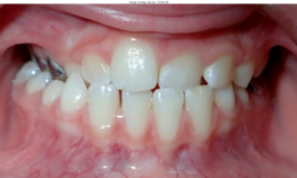

| Partial Anterior Crossbite | 1 or 2 of the top front teeth are behind the bottom front teeth and the rest are in front | ![]() | Limited braces (on the front teeth) to align the front teeth and correct the crossbite |